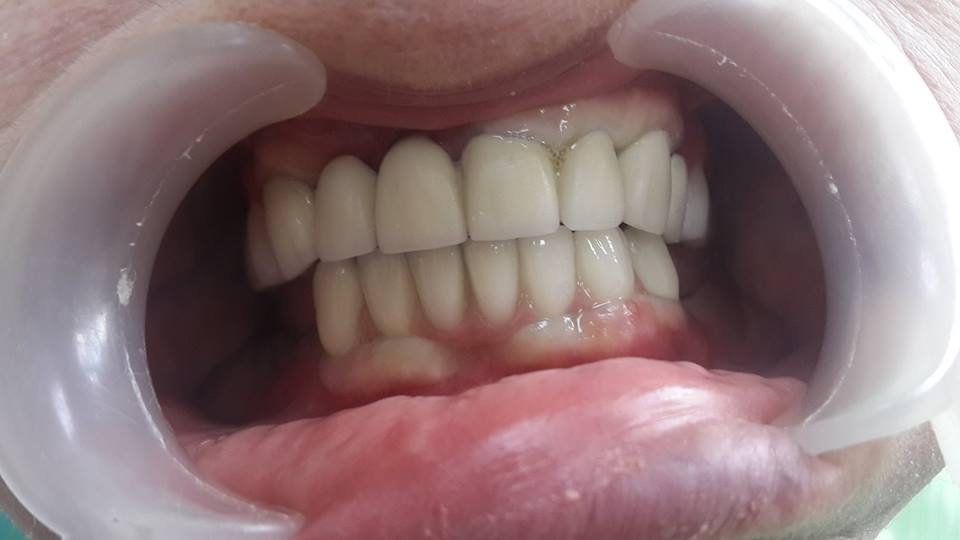

An example of complete rehabilitation of the oral cavity. Treatment included the removal of the old prosthesis, treatment of paradontitis, removal of a large cyst, implantation, clasp prosthesis.